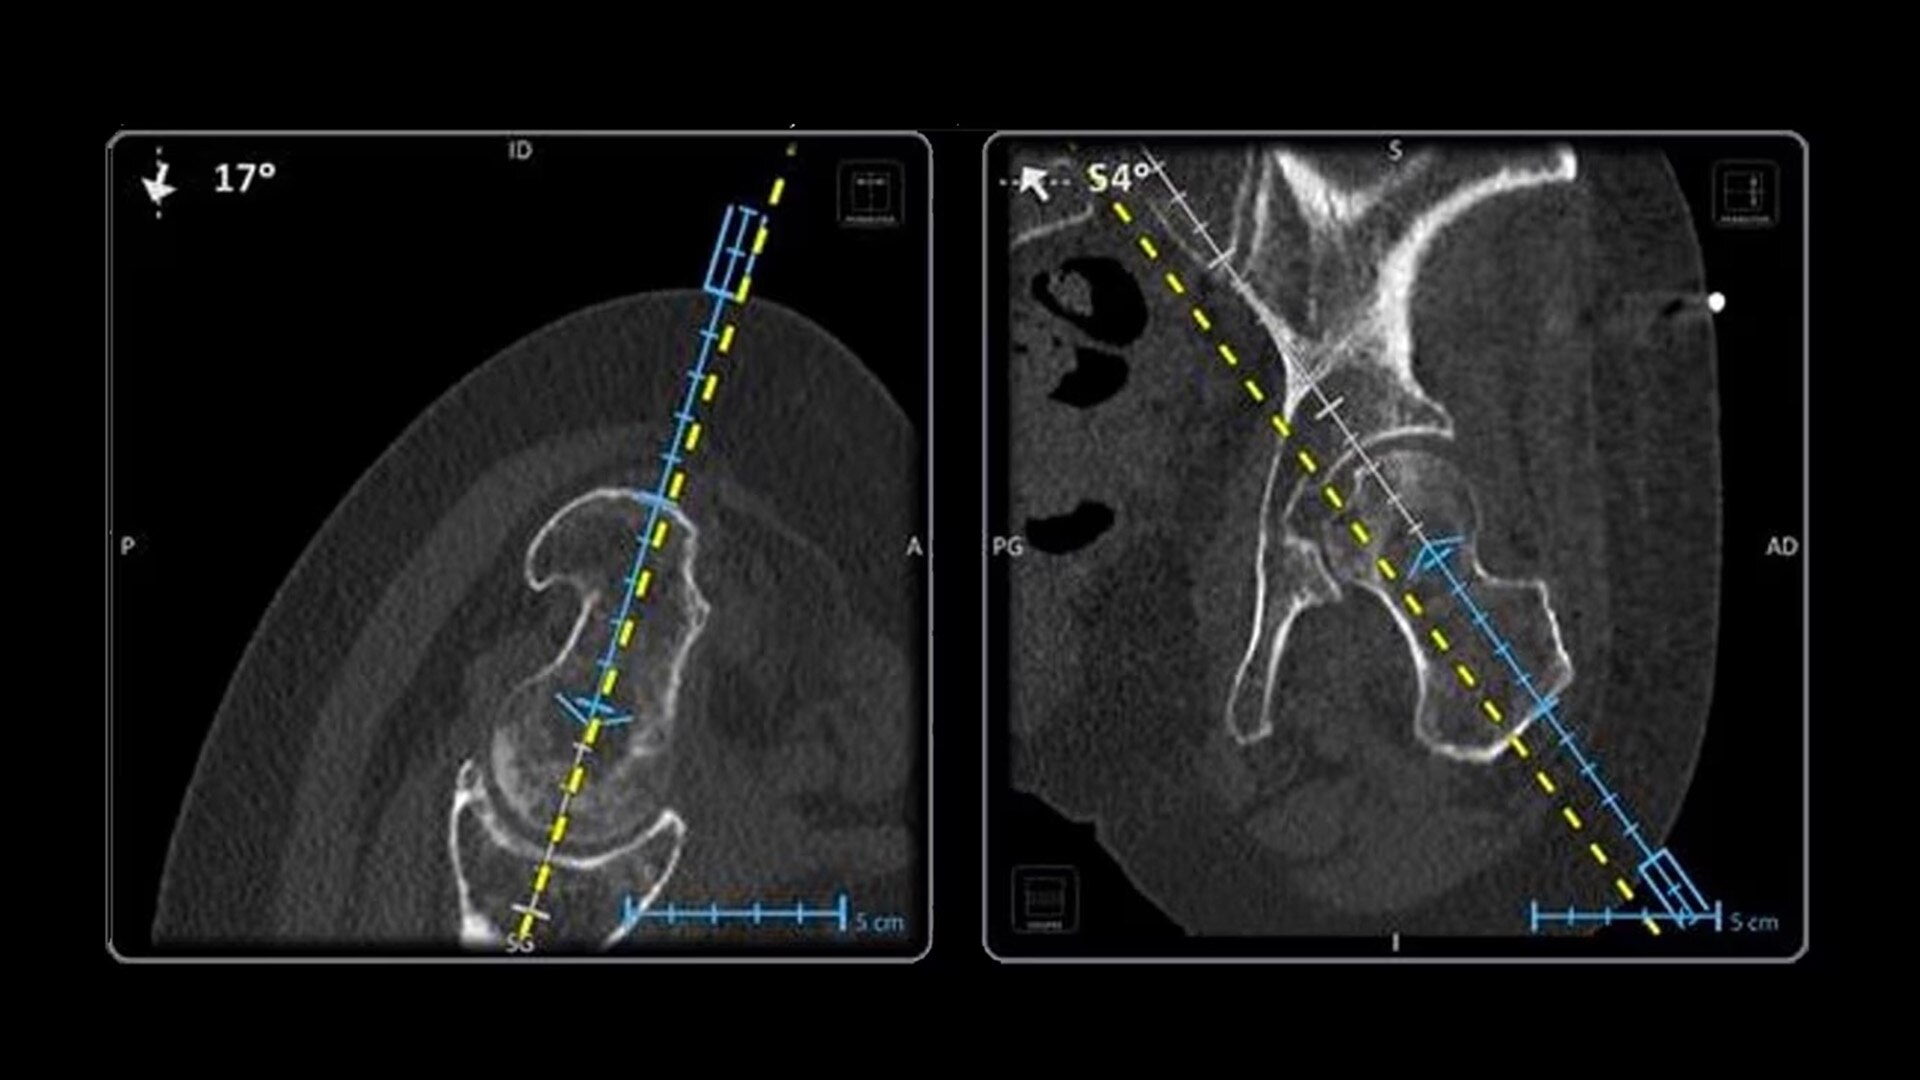

In interventional radiology, the success of the percutaneous procedure depends on correct needle positioning. The Imactis system helps the radiologist place one or more needles with great accuracy, in less time and with fewer control scans.

Versatility

Fully compatible with any type of needle, from 25 gauge to 11 gauge, Imactis can be used for a wide variety of procedures.

The CT navigation solution optimizes the efficiency and potentially helps to improve clinical outcomes of biopsies, thermoablations, drainages, infiltrations, electroporations and osteosynthesis.

Imactis enables you to find the ideal path to the target.

With real-time image reconstruction, live interactive navigation and no limit in angulation, the optimal clinical choices are clear.

Live 3D needle tracking, precise reproduction of your planned trajectory and continuous needle depth measurement help ensure optimal needle placement.